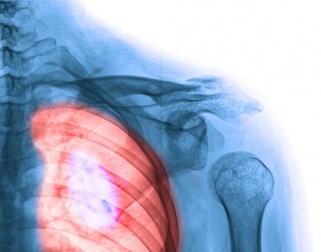

4. La douleur dans le thorax

La douleur dans le thorax est une des caractéristique des symptômes du cancer du poumon.

Nous ressentons une certaine lourdeur dans la poitrine et de la gêne au moment de respirer, à cause de possibles problèmes dans la plèvre ou dans les côtes.